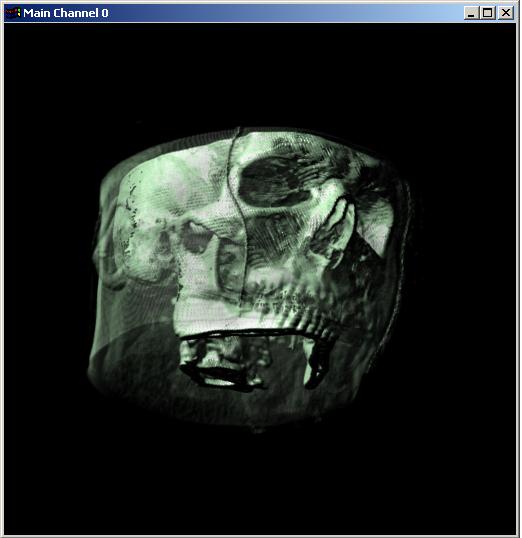

Visible human male CT data

Data

Resolution : 256x256x128

The following 12

images was generated by PC which has NVIDIA's GeForce3 GPU graphics card. The

hardware accelerated rendering techniques are used to make the following images.

To use the GeForce3 hardware, we have to use the OpenGL extensions like

GL_NV_texture_shader2, GL_NV_register_combiners, GL_EXT_texture3D,

GL_EXT_paletted_texture, GL_ARB_multitexture and so on. Since the GeForce3 card

allows the 3D texture shading, the image quality is better than the pixel of

frame buffer based shading in showing two materials at the same time.